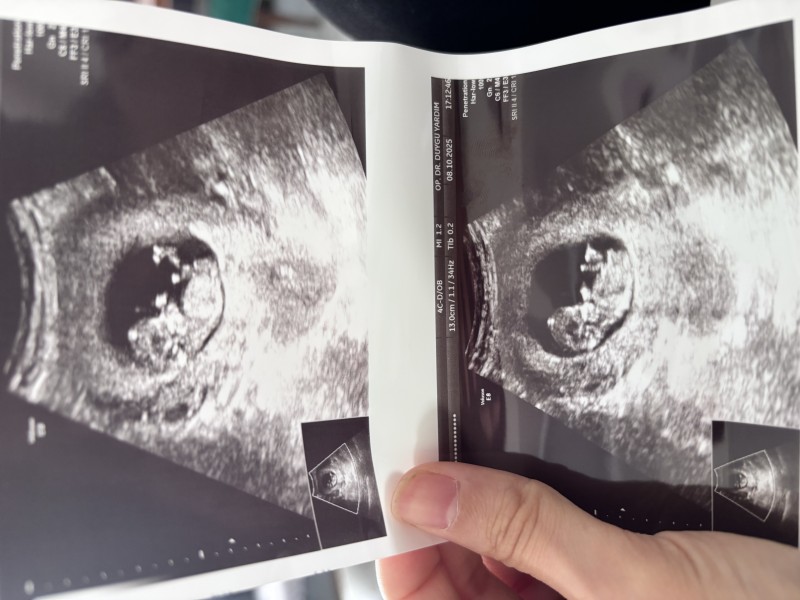

Kızlar cinsiyet tahmini nasıl neye göre yapılıyor hiç anlamıyorum ama bende bi sormak istedim bana da tahmin yapabilir misiniz 😊

image

Başı büyük, tepesi yassı duruyor. Erkek diyorum.

Keseye göre dersek benimki de böyleydi kız bebek oldu

Benim bebegime benziyor kiz

Kesin erkektir öğrendiğimde bana yaz

Kız bence canım ögrenince yaz mutlaka canım yine doğru yanlış mı bilicem:)

Ayy aynı haftada benimde aynı böyleydi ultrason fotorafım hatta cok kibar bence kız diyordum ama ogluşum oldu :))